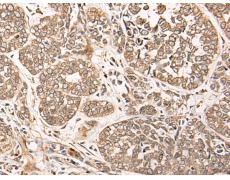

IHC positive control: |

Human esophagus cancer |